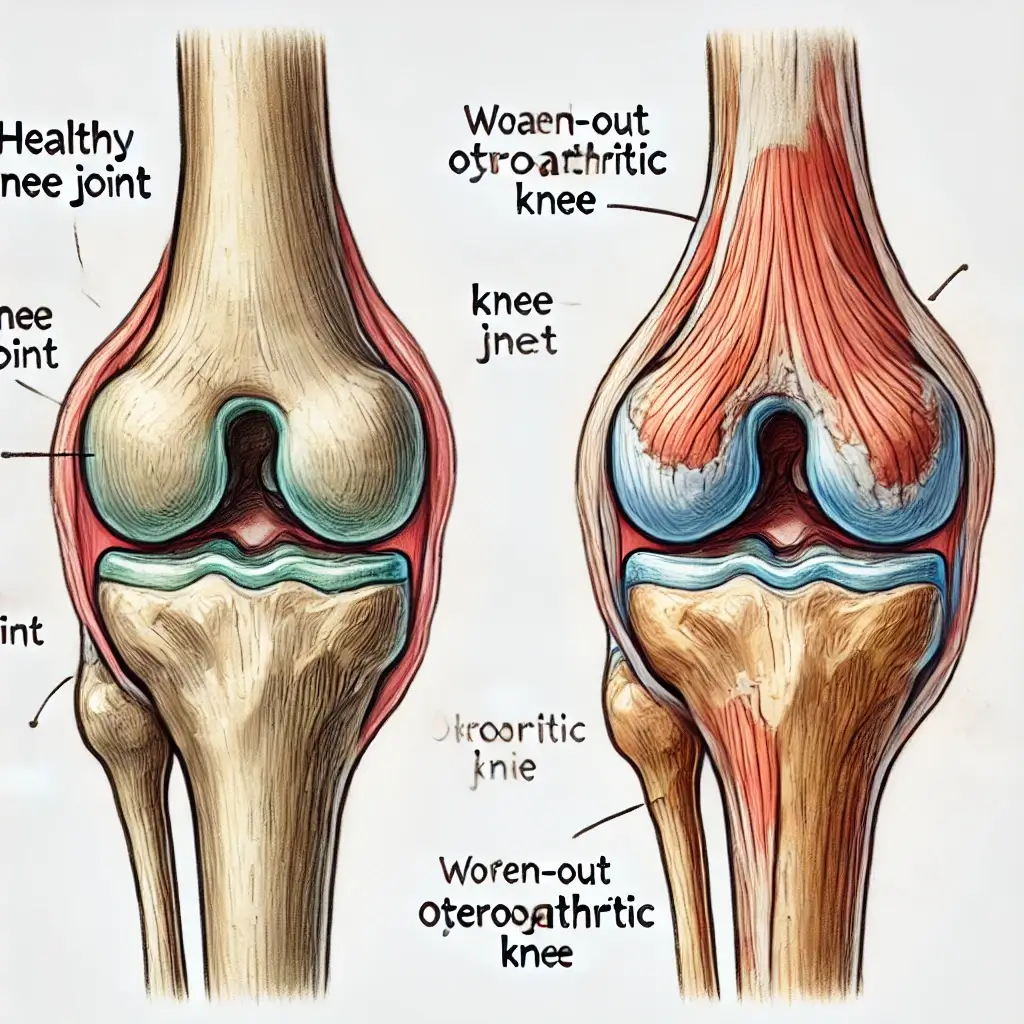

골다공증 초기증상은 눈에 잘 띄지 않아 많은 이들이 놓치기 쉽습니다. 뼈는 겉으로 드러나지 않지만 조용히 약해지고 있습니다. 사소한 허리 통증이나 무릎 불편감도 골다공증 초기증상일 수 있습니다.

골다공증 초기증상은 일상 속 사소한 불편으로 나타납니다. 무릎이 시큰거리거나 오래 서 있기가 힘들고, 이전보다 허리가 자주 아프다면 뼈 건강을 의심해봐야 합니다.

아침에 일어났을 때 뻣뻣함이 심하거나, 자세를 바꿀 때마다 뼈 마디가 욱신거리는 느낌도 골다공증 초기증상일 수 있습니다.

이처럼 골다공증 초기증상은 작지만 반복되는 통증으로 시작되며, 뼈 손상이 누적되면 골절 위험이 급격히 높아지므로 빠른 관리가 필요합니다.